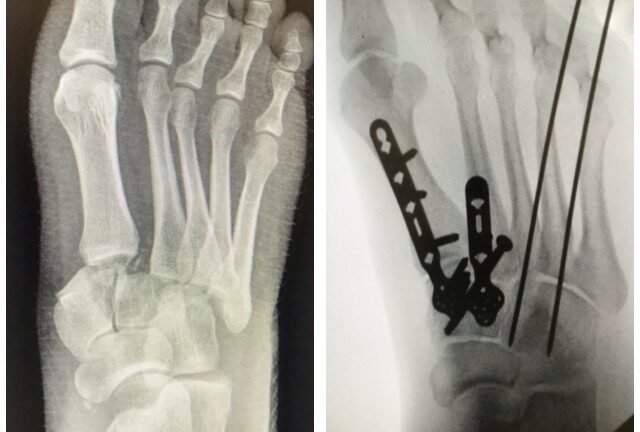

Murtumakuvia

Ennen – Jälkeen